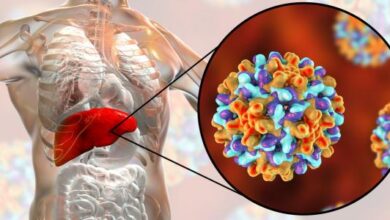

يتمثل التهاب الكبد بحدوث التهاب في خلاياه وتلف واضح فيها، وتوجد عدة أنواع لالتهاب الكبد، منها التهاب الكبد الفيروسي أ، والتهاب الكبد الفيروسي ب، والتهاب الكبد الفيروسي ج، وقد سُمّي كلّ منها باسم الفيروس المُسبب له، وأمّا بالنسبة لعلاج هذه الالتهابات فيمكن تلخيصها فيما يأتي:[٢]

- التهاب الكبد الفيروسي أ: عادة ما يُشفى المصابون بهذا النوع من الالتهابات دون اللجوء للعلاجات الطبية، ويُنصح المصابون بهذا الالتهاب بالامتناع عن شرب الكحول وتعاطي المخدرات والأدوية غير المشرعة قانونيًا، وتجنب أخذ أي دواء دون استشارة الطبيب.

- التهاب الكبد الفيروسي ب: يعتمد علاج هذا الالتهاب على أخذ المصاب قسطًا وفيرًا من الراحة، إلى جانب الامتناع عن شرب الكحول، وقد يصف الطبيب في بعض الحالات أحد مضادات الفيروسات المناسبة بما في ذلك الإنترفيرون (بالإنجليزية: Interferon).

- التهاب الكبد الفيروسي ج: قد يصف الطبيب لعلاج هذا الالتهاب مضادًا للفيروسات إلى جانب ريبافيرين (بالإنجليزية: Ribavirin) في بعض الحالات، وإنّ معدل التعافي من التهاب الكبد الفيروسي ج عالٍ للغاية في حال الالتزام بالخطة العلاجية التي يصفها الطبيب.

ولمعرفة المزيد عن علاج التهاب الكبد الفيروسي يمكن قراءة المقال الآتي: (علاج التهاب الكبد الفيروسي).

ولمعرفة المزيد عن علاج التهاب الكبد الفيروسي ج يمكن قراءة المقال الآتي: (علاج التهاب الكبد الوبائي c).